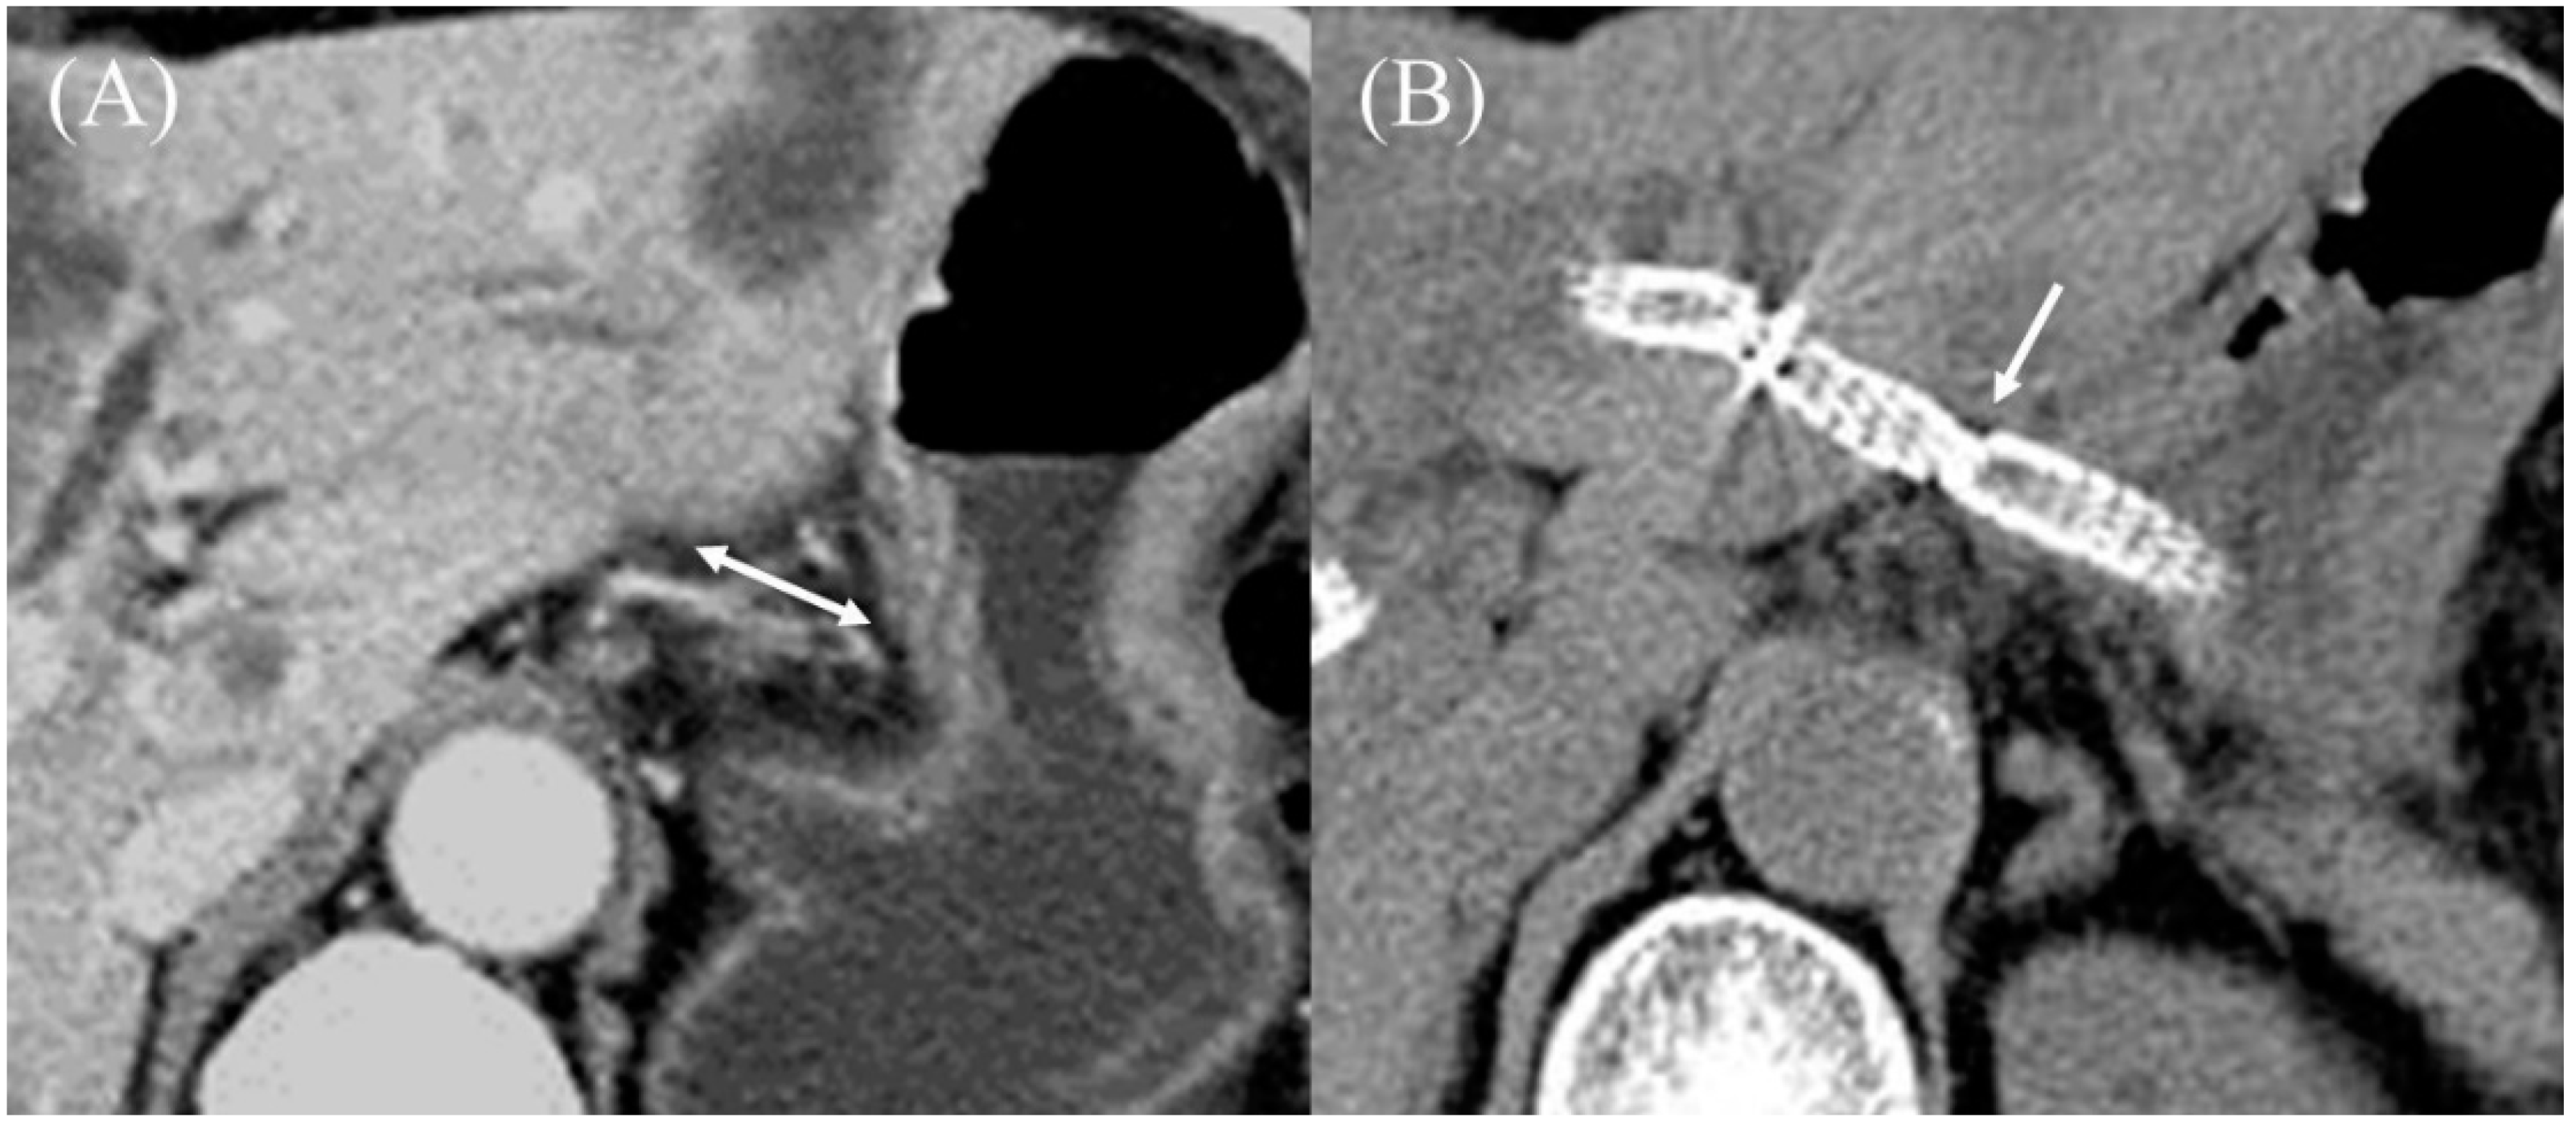

Figure 20.

Endoscopic ultrasound-guided hepaticogastrostomy with a Covered BileRush Advance. Pre-procedure contrast-enhanced CT showed a long distance between the gastric body and left hepatic lobe (double arrow) (A). Post-procedure CT showed the Covered BileRush Advance fixed the gastric body near the left hepatic lobe by its jagged surface (arrow) (B).

There are several SEMSs with a slim introducer allowing direct insertion without prior tract dilation. From Korea, HANAROSTENT Benefit (M.I.Tech, Seoul, Korea) [22,81,82] and EGIS Braided 6 (S&G Biotech, Seongnam, Korea) [83], which are fully covered SEMSs with a 6 Fr introducer for a 0.025 inch guidewire, have been released. In most cases, these SEMS can be inserted without prior dilation. Nevertheless, since these SEMS are of the fully covered type without any anti-migration properties, migration of both sides is feared. In addition, since the bile ducts on the peripheral side of the access point are dead spaces, these SEMS are not only unsuitable for hilar biliary obstruction but may also cause focal cholangitis in the dead spaces [84]. Most recently, Covered BileRush Advance (Piolax Medical Devices), a partially covered SEMS with a 2 cm uncovered portion at the hepatic end, has been launched (Figure 19A). This stent has an introducer compatible with a 0.025 inch guidewire that has a 2.4 Fr tip and a 7 Fr shaft and can be inserted directly without dilation in most cases (Figure 19B). Because this stent is a laser-cut type, the stent expands rapidly in the stomach from a non-expanded area in the gastric wall, resulting in a steep stent surface. This incised shape and jagged struts inhibit gastric wall return to its original position (Figure 20A,B); furthermore, there is almost no shortening of the stent, which results in little delayed migration [85]. One-step EUS-HGS without prior tract dilation has the potential to reduce adverse events and procedure time compared to conventional methods, and further studies are warranted.